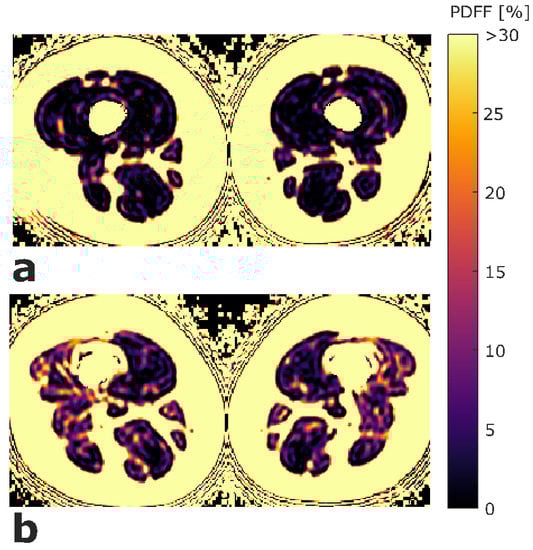

ROIs were placed at the muscle contour to minimize the inclusion of subcutaneous fat or the muscle–fat interface. A representative PDFF map with corresponding segmentation masks of EXT and FLEX muscles is shown in Figure 1. Mean PDFF of each of the four muscles was extracted. Mean PDFF values were calculated of EXT and FLEX for the left and right side, respectively, to obtain values for both muscle groups on both sides (PDFFEXT,left, PDFFEXT,right, PDFFFLEX,left, and PDFFFLEX,right). Sample color-coded PDFF maps of two subjects, one with high strength and low mean PDFF, and one with low-strength and high-mean PDFF are shown in Figure 2.

Figure 2.

Exemplary color-coded axial PDFF maps of two study participants. (a) Participant with high strength (left side: MVICEXT = 281.7 Nm, MVICFLEX = 113.5 Nm; right side: MVICEXT = 298.7 Nm, MVICFLEX = 147.0 Nm) and low mean PDFF values (left side: PDFFEXT = 1.07%, PDFFFLEX = 1.46%; right side: PDFFEXT = 0.31%, PDFFFLEX = 0.98%). (b) participant with low strength (left side: MVICEXT = 126.7 Nm, MVICFLEX = 77.2 Nm; right side: MVICEXT = 149.1 Nm, MVICFLEX = 68.1 Nm) and high mean PDFF values (left side: PDFFEXT = 5.31%, PDFFFLEX = 6.94%; right side: PDFFEXT = 4.71%, PDFFFLEX = 8.59%). The upper limit of the color window was set to 30% to better depict the PDFF values within the thigh muscles. (PDFFEXT/FLEX, proton density fat fraction of quadriceps and ischiocrural muscles; MVICEXT/FLEX, maximum voluntary isometric contraction of extension and flexion; Nm, newton meter).